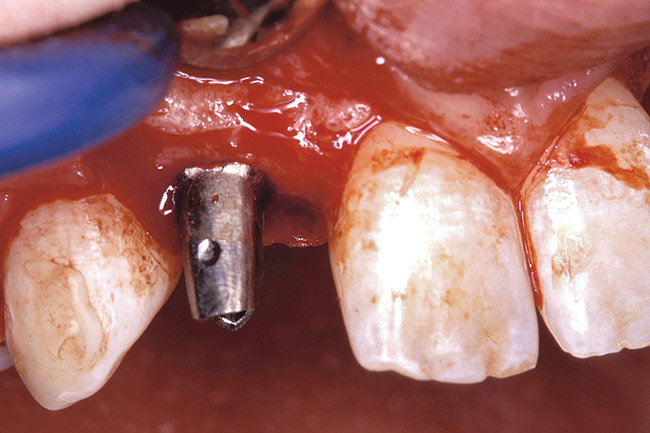

Figure 2  DIAGNOSTIC INFORMATION Root convergence, buccal view.

Figure 2

Periapical radiographs were taken to help determine the mesial-distal inclinations of the adjacent tooth roots (Figure 1). The radiographs revealed a serious issue, convergent roots for the right canine and right central, which eliminated that area as a potential implant-receptor site. The space between the left central and canine teeth was minimal, although the roots were relatively parallel. Clinical examination (manual palpation of the root eminences superiorly to the vestibule on the right side) confirmed the root convergence (Figure 2). The flat, wide zone of the keratinized tissue and lack of interdental papilla was evident for the missing right lateral incisor. There was a marked difference in clinical appearance for the left lateral, which could impact the eventual plan of treatment (Figure 3). Other significant clinical findings included bilateral facial bone concavities, which existed as a result of the congenitally missing tooth roots. As a diagnostic cue to the underlying bone topography, it is important to follow the demarcation between attached and unattached gingival tissue, and note the crestal width of the available keratinized tissue (Figure 4).